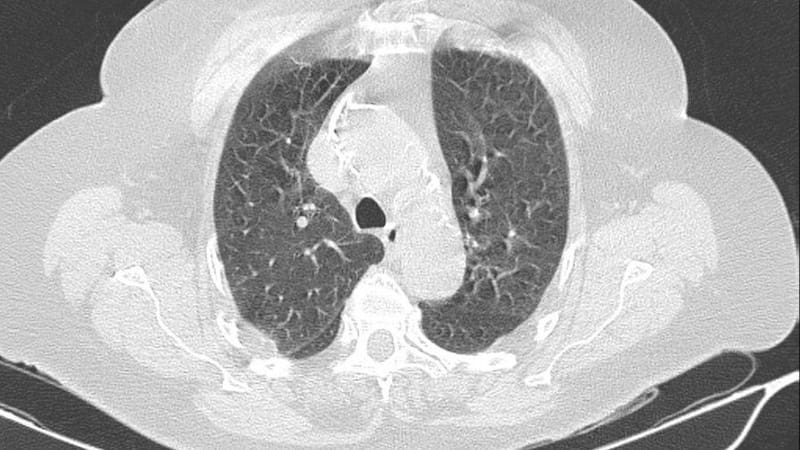

Ronald Reid, broncopulmonar y médico jefe del Servicio de Medicina de Clínica Universidad de los Andes, señala que el daño a los pulmones por el coronavirus tiene dos fases. “Primero, una fase inflamatoria muy importante, en la cual el virus produce un daño directo a nivel de las células del epitelio, que es el tejido que cubre los alvéolos o los bronquios. Eso finalmente produce una cascada inflamatoria, que hace que los alvéolos se llenen de líquidos con células inflamatorias, se ocupe el espacio e impide que puedan funcionar".

“Es decir, lo primero que se ve es una neumonía, que es con características de tipo inflamatoria, y eso produce una falla respiratoria severa y los pacientes pueden caer en ventilación mecánica o cosas así”, explica Reid.

“Todo el material inflamatorio que produce el coronavirus, va generando áreas de infiltración e inflamación en el pulmón, y finalmente toda la unidad se va rellenando de un material inflamatorio dado por elementos solubles y también por células que van obstruyendo el flujo y van generando los síntomas”, explica Beltrán.